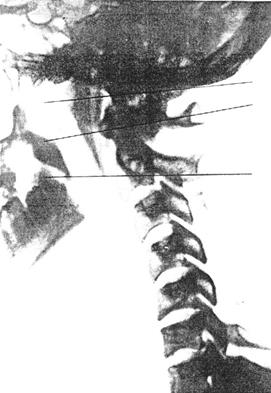

Рис. 54 Рентгенодиагностика функционального блока атласа (С0-1)

а) Функциональный блок атласа (Со -1) в направлении ротации влево, латерофлексии вправо

в) Функциональная проба в направлении латерофлексии шейного отдела позвоночника (признаки ФБ Со - i, Ci - 11)

Отсутствие подвижности между затылком и атласом, атласом и зубом

с) Функциональная проба в направлении латерофлексии шейного отдела позвоночника после проведённой манипуляции. Восстановлена подвижность между затылком и атласом